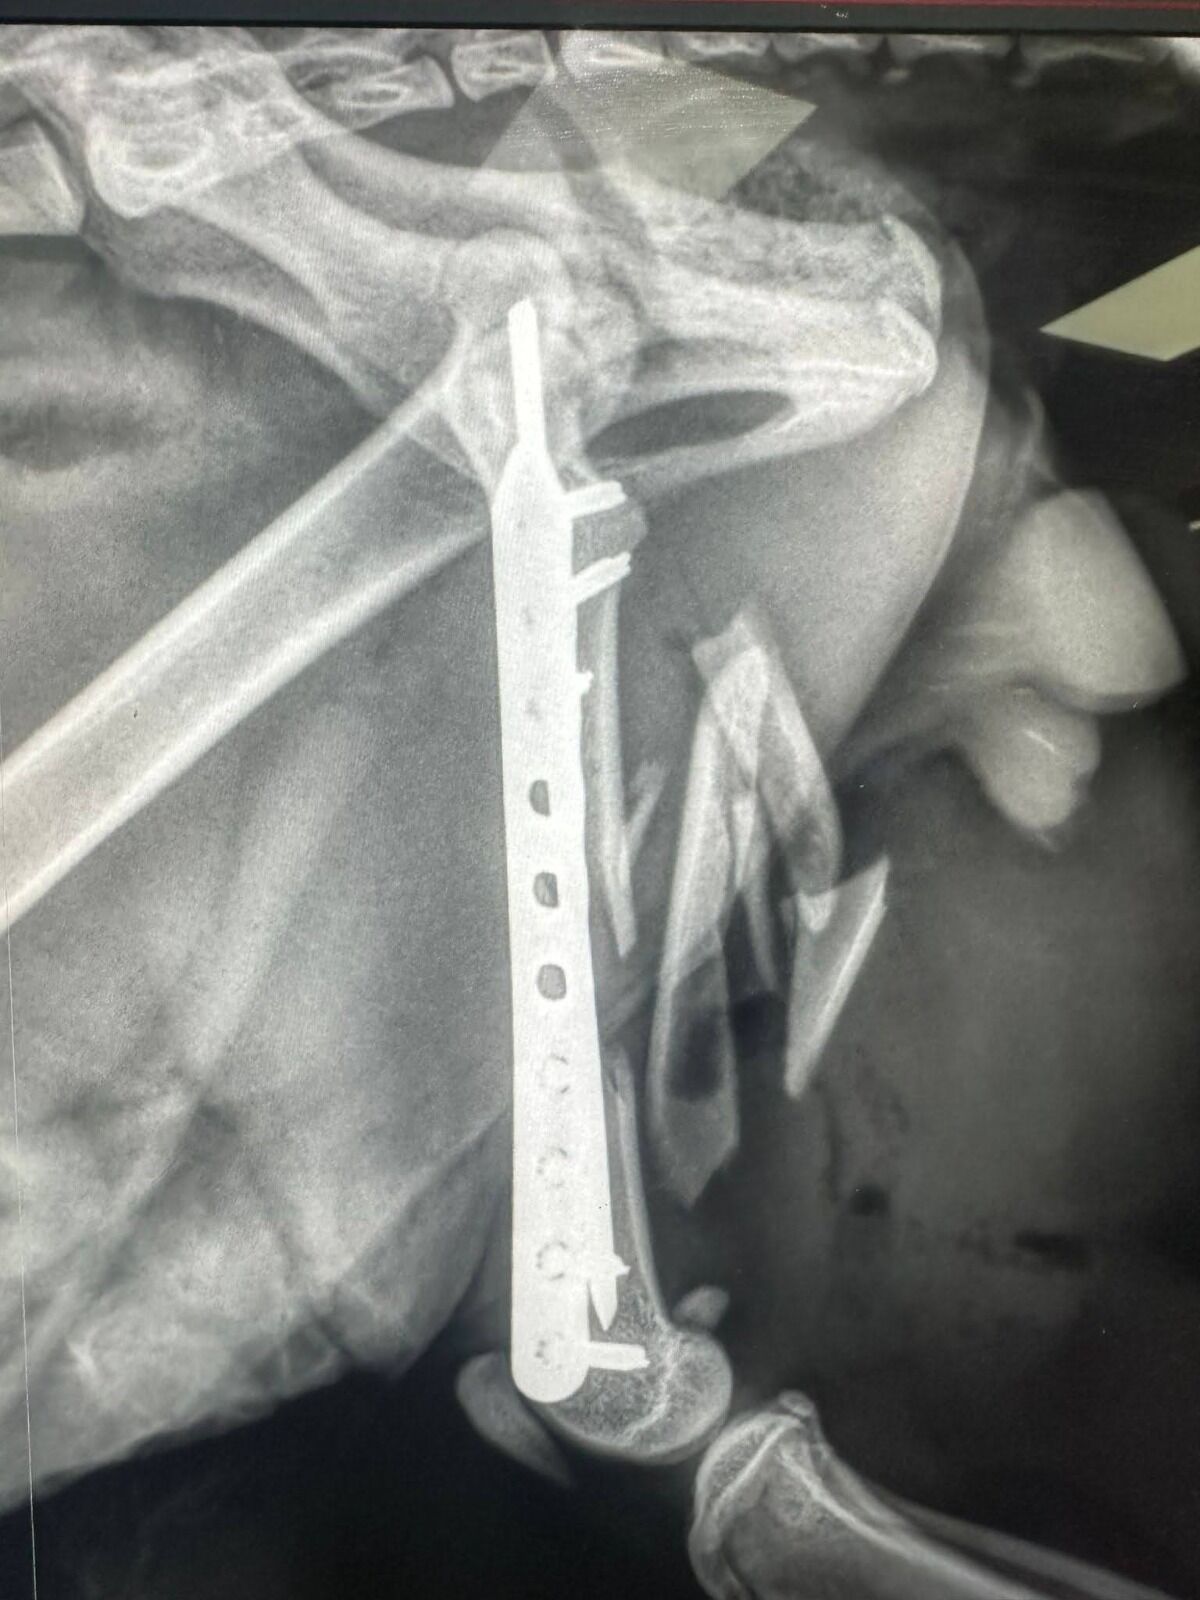

תושבי העיר זיהו חתול רחוב צולע בעיר והזעיקו את השירות הווטרינרי של עיריית רחובות. צוותי השירות הווטרינרי אספו את החתול לבדיקה רפואית בה גילו כי הרגל שלו שבורה ונמצאת במצב קשה.

צוותי השירות הווטרינרי של עיריית רחובות בסיוע בית החולים הווטרינרי "טיפול נמרץ" בכפר הנוער בן שמן טיפלו בו במסירות והכניסו אותו לניתוח אורטופדי מורכב במיוחד לתיקון השבר.